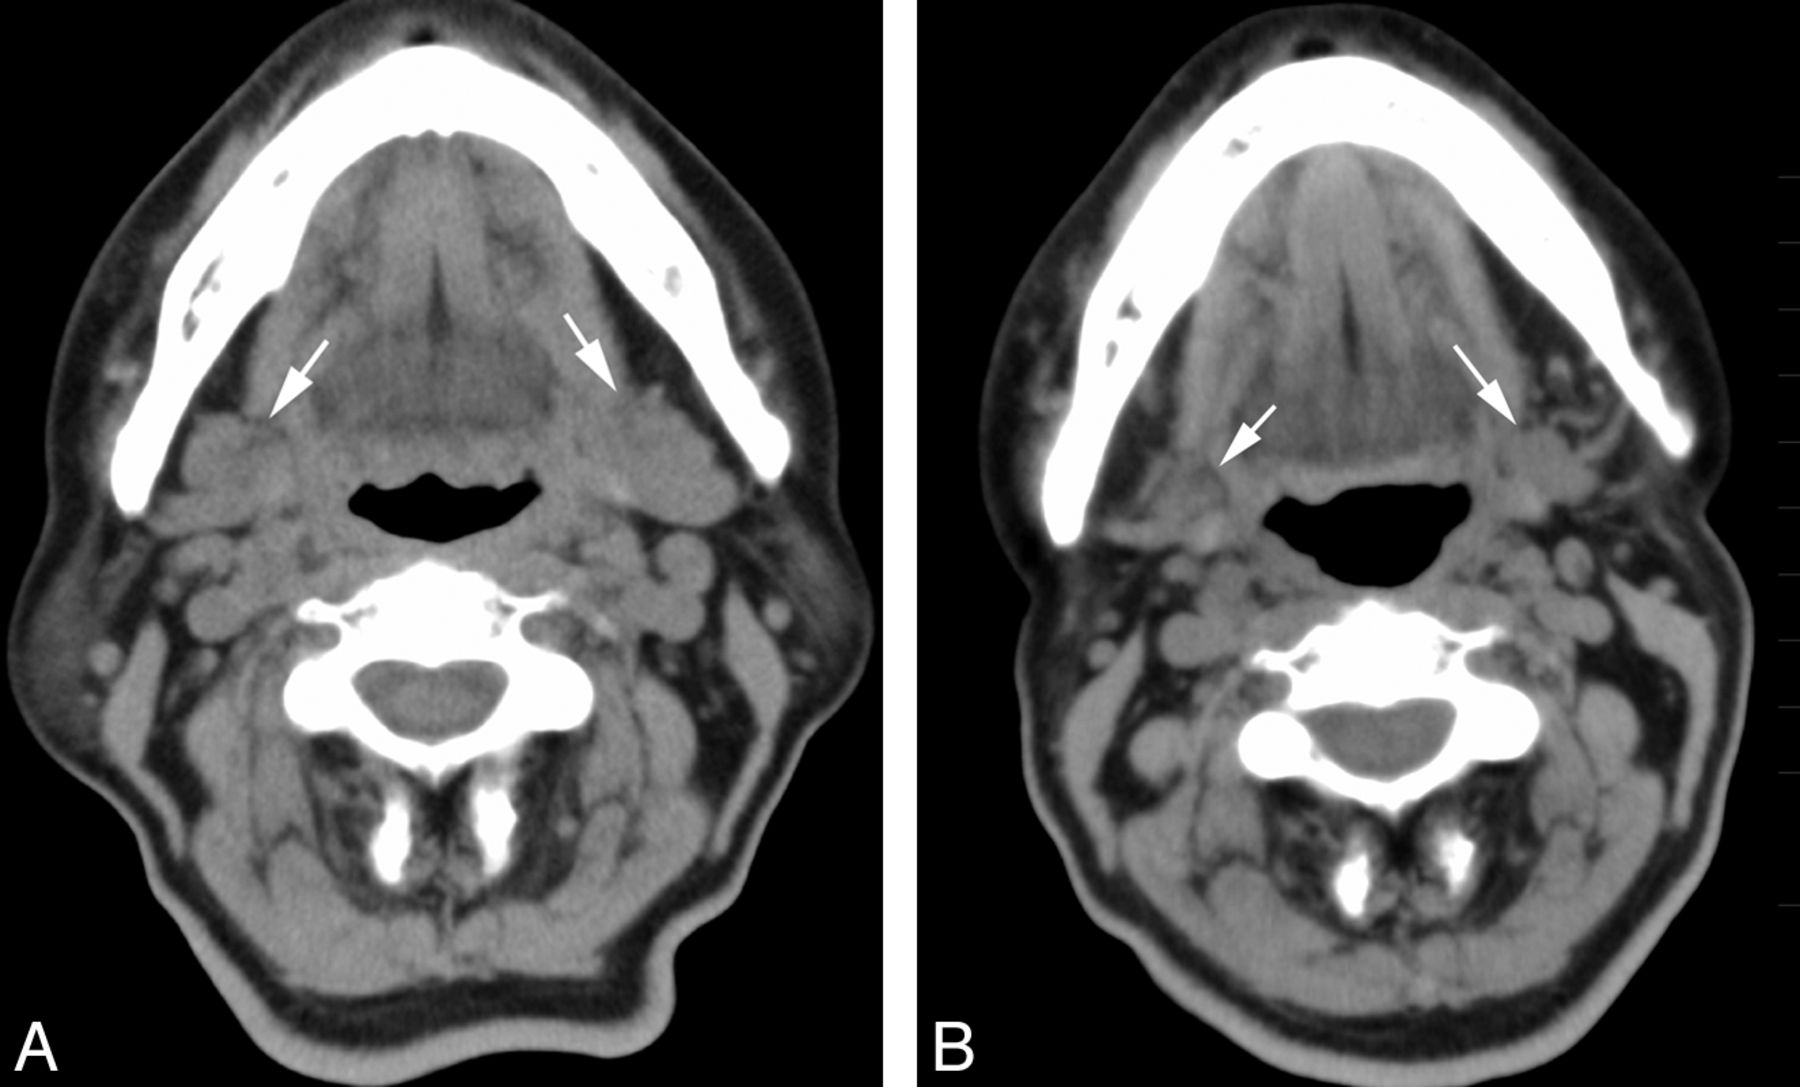

The reduction volume (mean ± SD; 95% confidence interval) in the parotid gland after RIT, depending on the grade of scintigraphy, was 2.5 ± 4.2% (0%–5.8%) for grade 1 (n = 9); 7.9 ± 5.2% (4.2%–11.7%) for grades 2 and 3 (n = 10); and 35.0 ± 13.9% (28.7%–41.4%) for grade 4 (n = 21) (Figs 1 and 2). The parotid gland volume after the treatment significantly decreased with an increase in the grade of dysfunction on scintigraphy (P < .001, 1-way analysis of variance). A significant difference in the reduction volume was present between grade 1 and grade 4 (P < .001) and grades 2 and 3 and grade 4 (P < .001) groups, but not between grade 1 and grades 2 and 3 groups, as determined by the Tukey Honestly Significant Difference test (Fig 3).

A 73-year-old woman who underwent 2 radioiodine treatments showed mild dysfunction of the parotid gland on scintigraphy. Non-contrast-enhanced CT images (A) before and (B) after the treatment. Bilateral parotid glands (arrows) showed only mild shrinkage (volume reduction of 12%) and an increase in attenuation (6 HU) on the CT scan obtained after the treatment.

A 71-year-old woman who underwent 3 radioiodine treatments showed severe dysfunction of the parotid gland on scintigraphy. Non-contrast-enhanced CT images (A) before and (B) after the treatment. The bilateral parotid glands (arrows) showed prominent volume reduction of 53% and an increase in attenuation of 32 HU on CT after the treatment.

The attenuation change (mean ± SD, 95% confidence interval) in the parotid gland after RIT, depending on the grade of scintigraphy, was 4.3 ± 3.7 HU (1.5–7.2 HU) for grade 1 (n = 9); 4.3 ± 3.4 HU (1.8–6.8 HU) for grades 2 and 3 (n = 10); and 23.9 ± 17.7 HU (15.8–31.9 HU) for grade 4 (n = 21) (Figs 1 and 2). The attenuation change in the parotid gland after the treatment significantly increased with an increase in the grade of dysfunction on scintigraphy (P < .001, 1-way analysis of variance). A significant difference in the attenuation change was present between the grade 1 and grade 4 (P < .002) and between the grades 2 and 3 and grade 4 (P < .001) groups, but not between the grade 1 and grades 2 and 3 groups, as determined by the Tukey Honestly Significant Difference test (Fig 6).